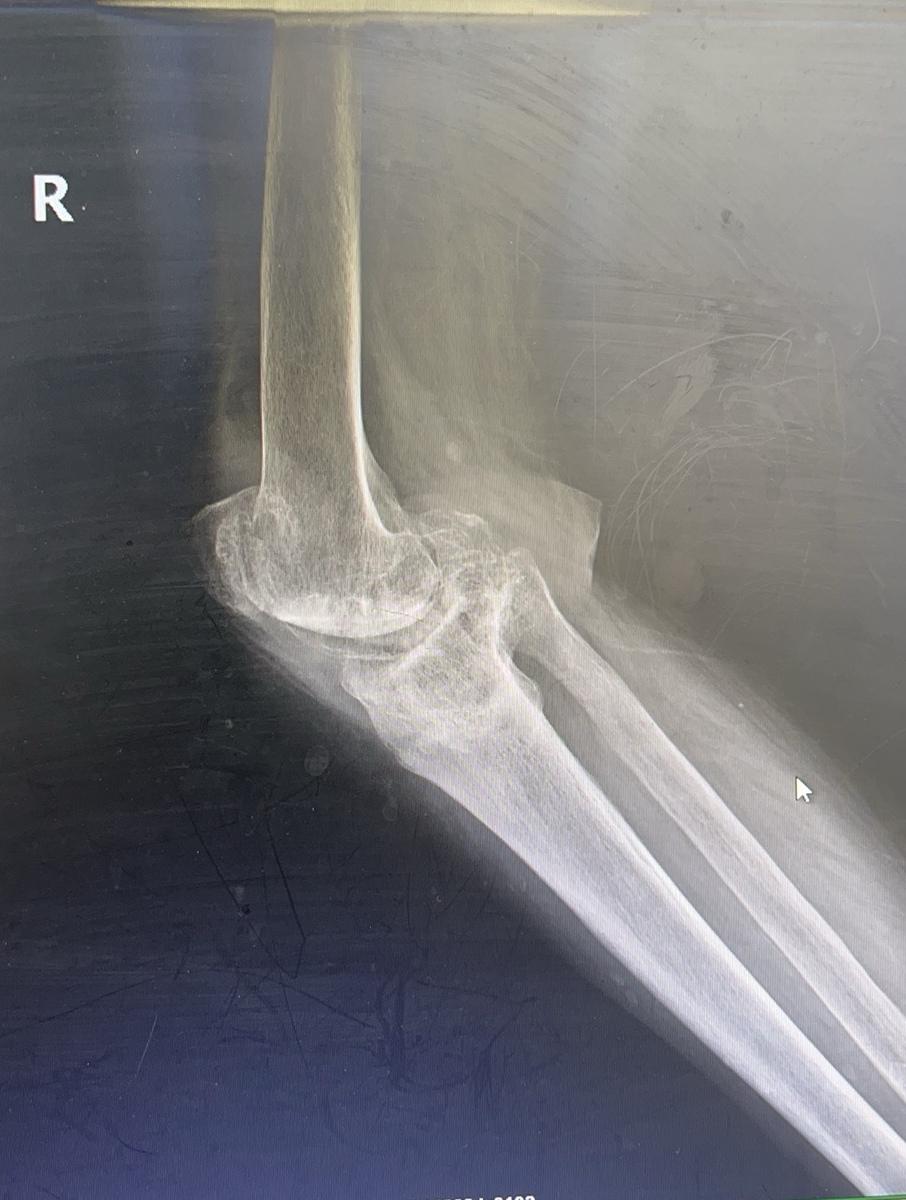

类风湿关节炎。类风湿关节炎,关节毁损,无法行走。备的CCK和铰链膝,最终CCK完美解决。用最小的代价给患者带来最大的获益🌹